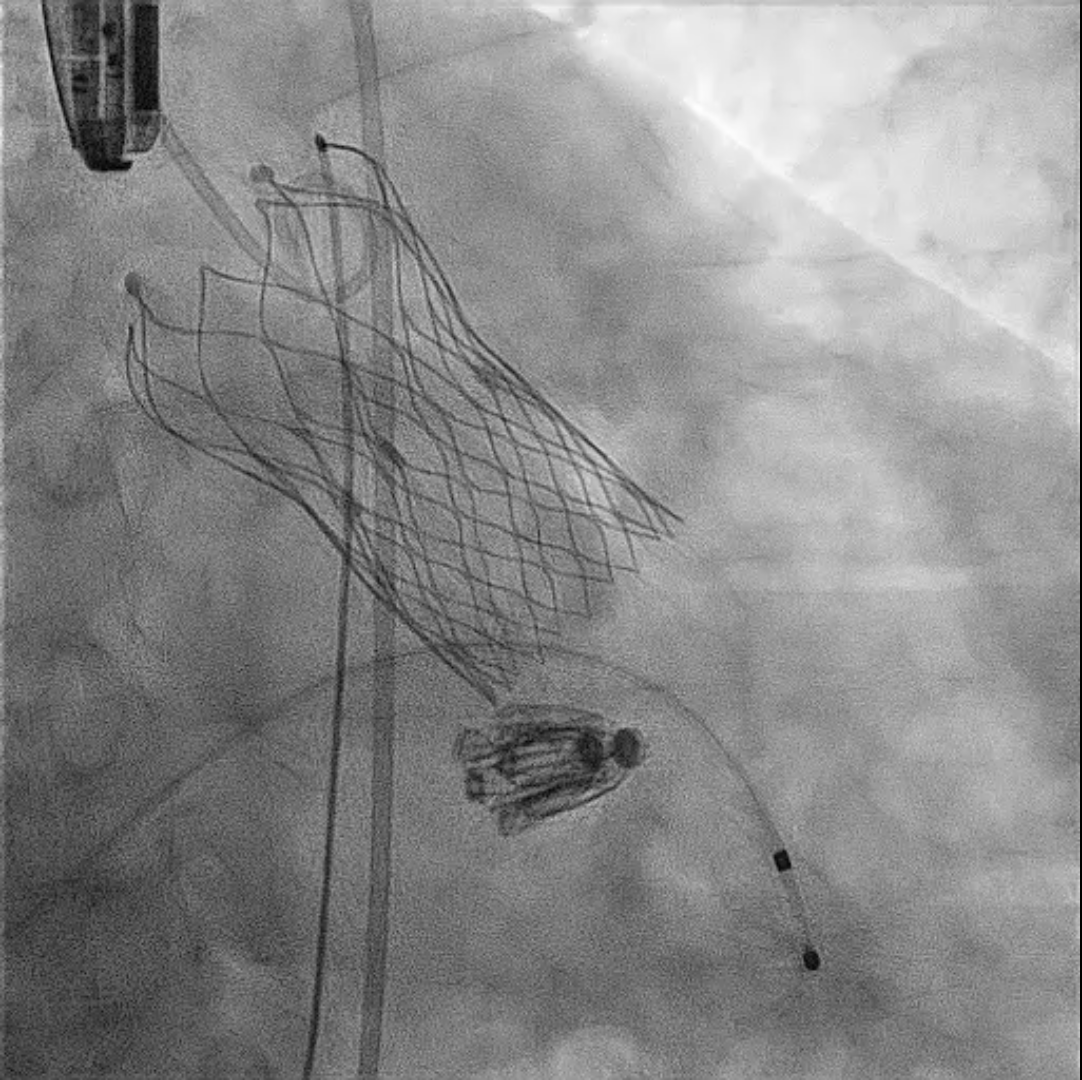

First, through the right femoral vein, the Neoblazar® delivery system (Dawneo Neoblazar, Hangzhou, China) was advanced till the tricuspid valve, and two clips (TMrCLAMP-S) were deployed to grasp the anterior and septal leaflets with a desired outcome reducing to a mild residual TR. Postoperative VC width was 0.2cm with EROA of 0.17cm2 and regurgitation volume of 15mL. The delivery system removed and 18 fr sheath exchanged. A 5 fr temporary pacemaker wire positioned through sheath into the right ventricle. Subsequently, the right and left femoral arteries were each accessed with 6-fr sheath and 22 fr sheath respectively. Through the left femoral artery, the TAVI delivery system with a 30mm VitaFlow Liberty™ self-expanding valve system (MicroPort®, Shanghai, China) was advanced across the aortic valve and deployed under transoesophageal and fluoroscopic guidance with rapid ventricular pacing at 140 beats/minute and pacing slowly tapered. The mean valvular gradient after TAVI decreased to 6 mmHg. Then, percutaneous access closure of arterial access was achieved using a pre-closure technique with the suture-mediated ProGlide device (Abbott Laboratories Inc., Chicago, Illinois, United States). The total procedure time was 60min. There were no intraoperative complications. The temporary pacemaker was removed two days later. Predischarge transthoracic echocardiogram showed a normal functioning aortic THV with a mean gradient of 6mmHg and mild residual tricuspid regurgitation.